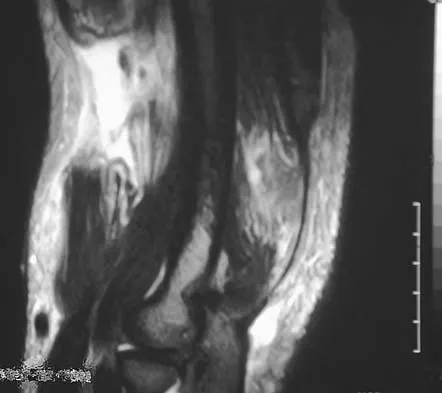

Figures 28a through 28c show the MRI scans of a 30-year-old woman who weighs 290 lb and has low back and left leg pain. She also reports frequent urinary dribbling, which her gynecologist has advised her may be related to obesity. Examination will most likely reveal

Explanation